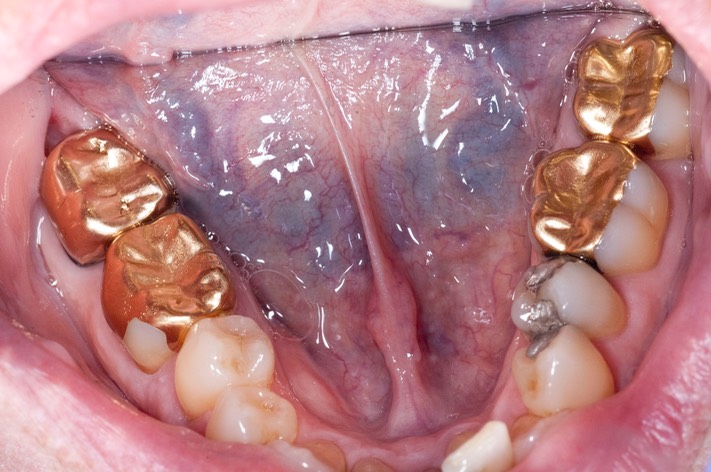

_DSC6230